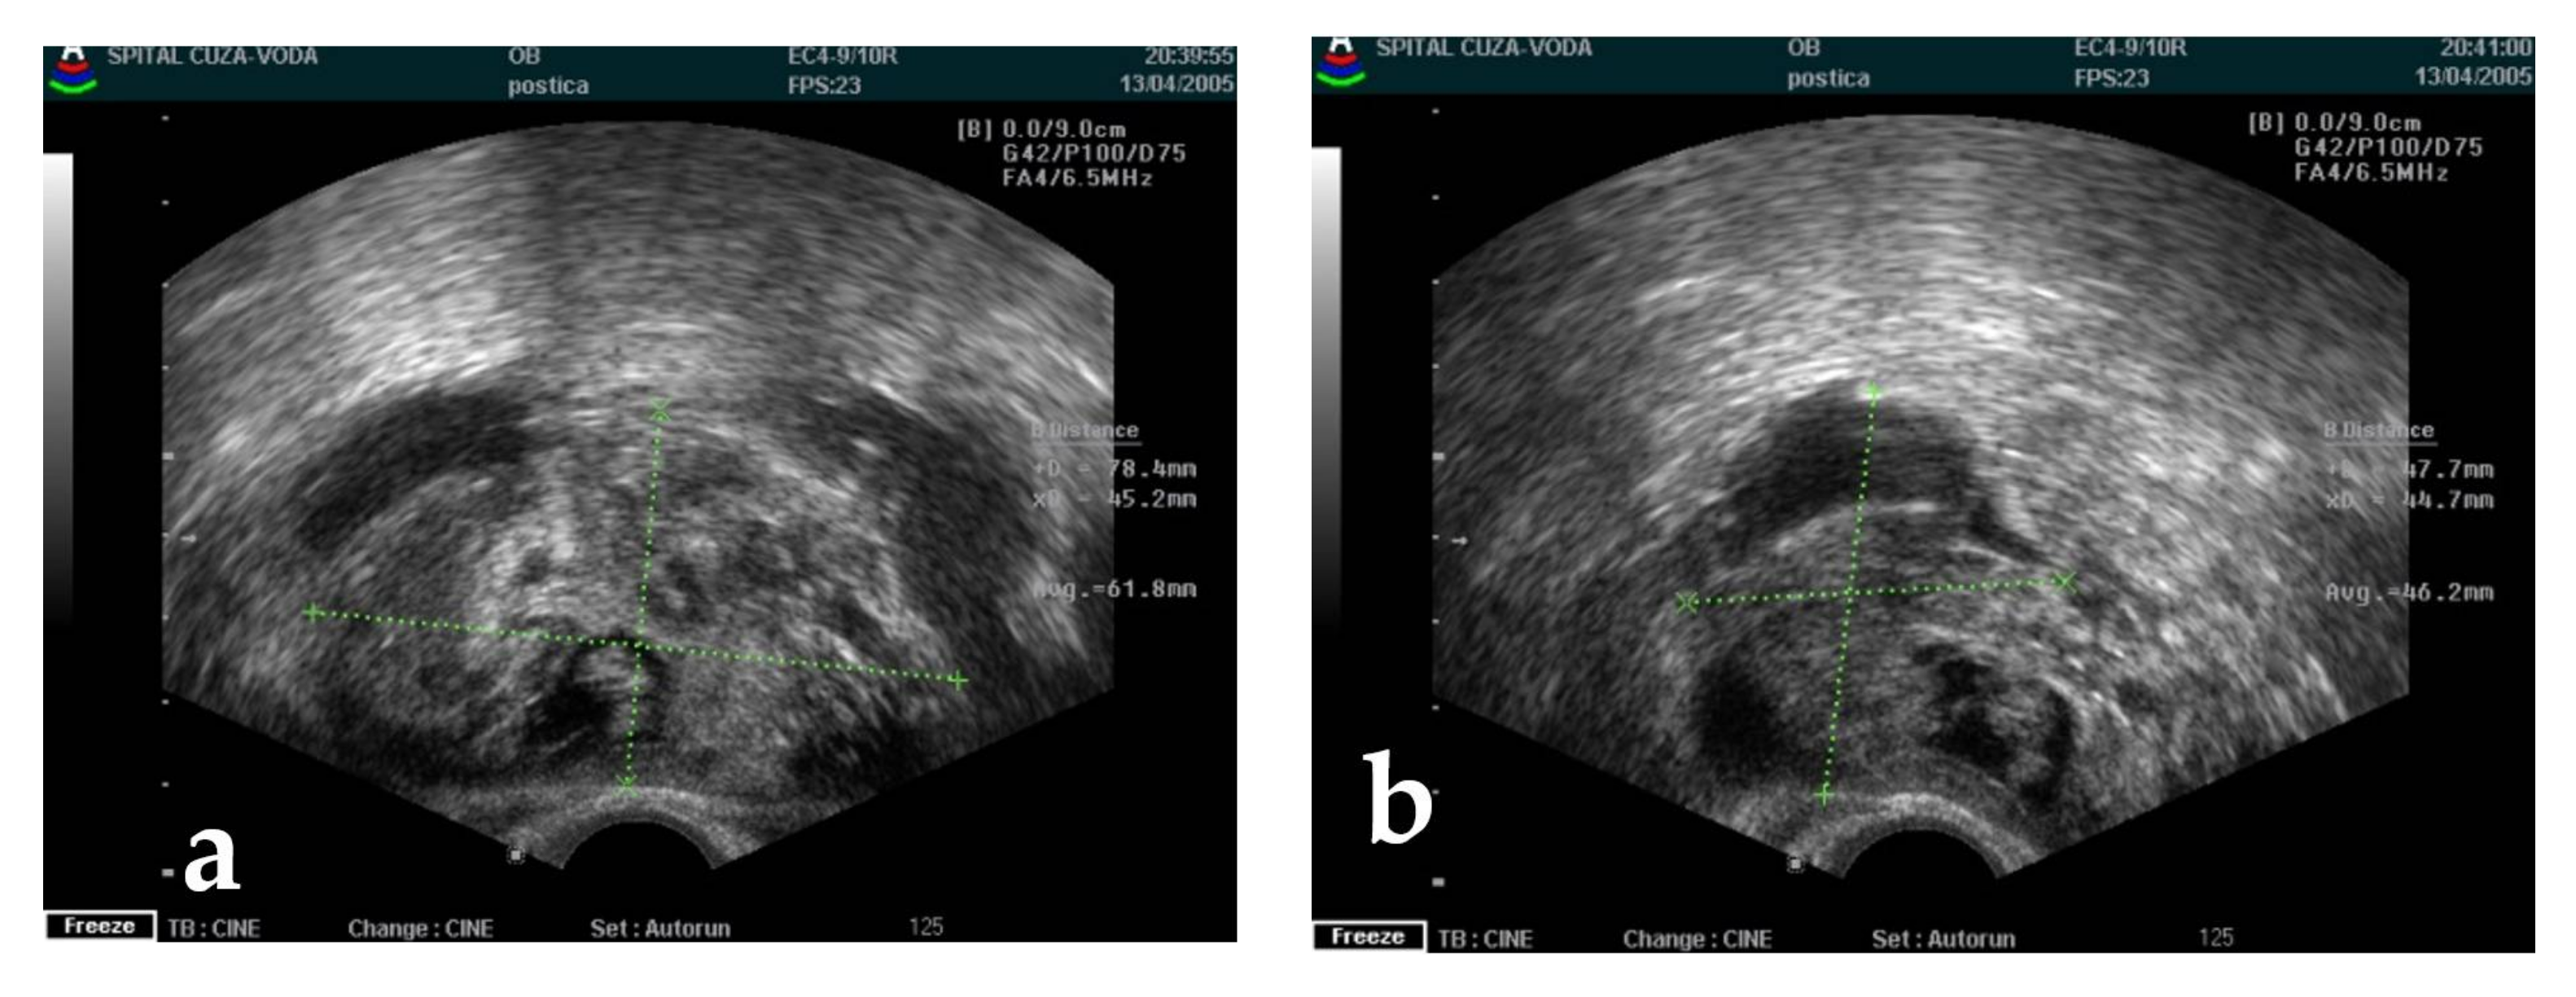

4.1. Diagnosis Approach

| 6 | 51 | right | 10 | 2005 | Serous cystadenoma Ascites | 45 |

| 7 | 35 | left | 2.5 | 2005 | Ovarian torsion Hyperthyroidism | 5.2 |

| 8 | 42 | left | 1 | 2005 | - | 3.1 |